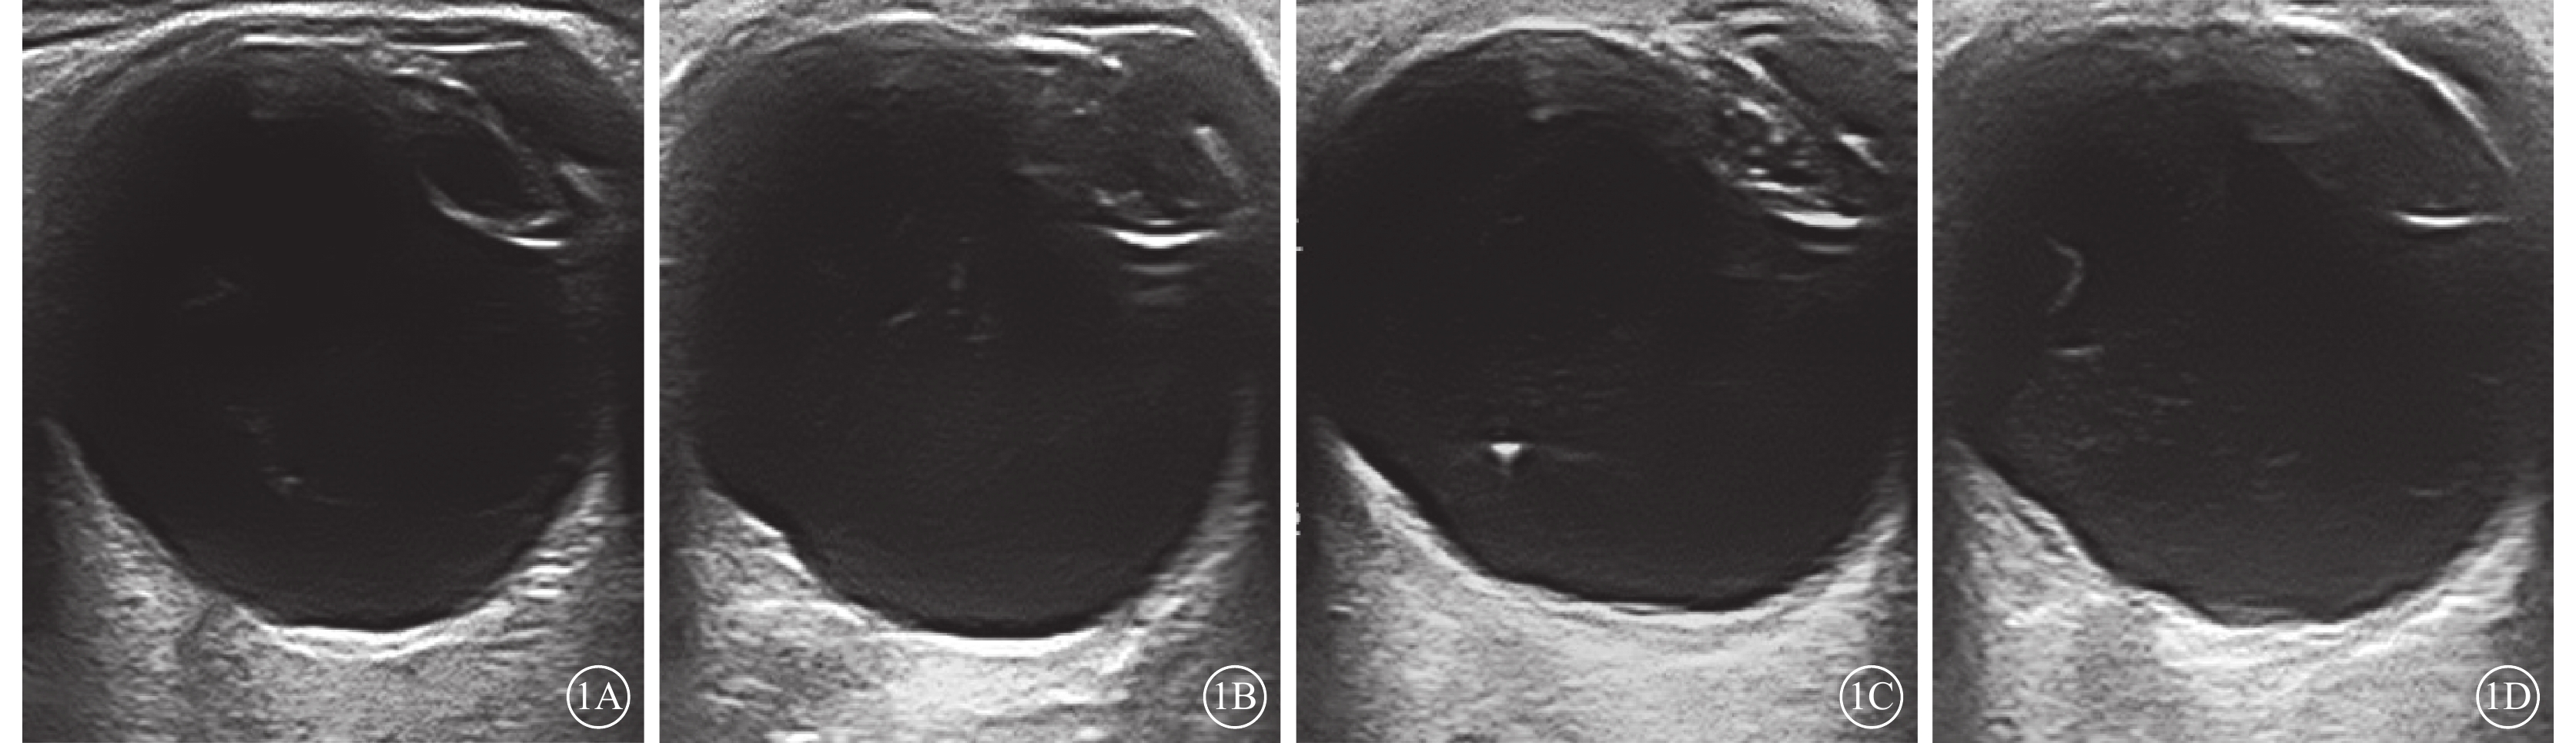

CDFI檢查結果顯示,1380只眼中,發現黃斑區異常回聲164只眼(11.9%)。異常超聲影像表現主要為:黃斑區球壁前膜狀回聲(圖1A)94只眼(6.8%);黃斑區球壁回聲局限隆起(圖1B)33只眼(2.3%);黃斑區球壁回聲增厚(圖1C)23只眼(1.7%);黃斑區球壁可見淺間隙(圖1D)11只眼(0.8%),其中病變表面探及血流信號8只眼(0.5%)。164只眼的平均CFT、AT分別為(393.75±138.47)、(323.64±50.41)μm。

圖1

老年性白內障患眼CDFI像。1A示黃斑區膜狀回聲;1B示黃斑區球壁回聲局限隆起;1C示黃斑區球壁回聲增厚;1D示黃斑區球壁可見淺間隙

圖1

老年性白內障患眼CDFI像。1A示黃斑區膜狀回聲;1B示黃斑區球壁回聲局限隆起;1C示黃斑區球壁回聲增厚;1D示黃斑區球壁可見淺間隙

CDFI檢查結果顯示,1380只眼中,發現黃斑區異常回聲164只眼(11.9%)。異常超聲影像表現主要為:黃斑區球壁前膜狀回聲(圖1A)94只眼(6.8%);黃斑區球壁回聲局限隆起(圖1B)33只眼(2.3%);黃斑區球壁回聲增厚(圖1C)23只眼(1.7%);黃斑區球壁可見淺間隙(圖1D)11只眼(0.8%),其中病變表面探及血流信號8只眼(0.5%)。164只眼的平均CFT、AT分別為(393.75±138.47)、(323.64±50.41)μm。

圖1

老年性白內障患眼CDFI像。1A示黃斑區膜狀回聲;1B示黃斑區球壁回聲局限隆起;1C示黃斑區球壁回聲增厚;1D示黃斑區球壁可見淺間隙

圖1

老年性白內障患眼CDFI像。1A示黃斑區膜狀回聲;1B示黃斑區球壁回聲局限隆起;1C示黃斑區球壁回聲增厚;1D示黃斑區球壁可見淺間隙